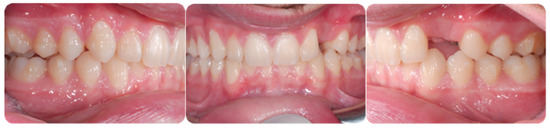

A 16-year-old male patient presented with a Class I occlusion, mild crowding, deep bite, and missing upper left cuspid with the absence of the respective deciduous. Light crowding can be detected in the maxillary arch, whereas no crowding was detected in the mandibular arch. The maxillary midline was coincident with the face and the mandibular midline. The radiographic analysis revealed a moderate impaction with a supernumerary tooth in the lower jaw between 3.5 and 3.4 ligually positioned and a skeletal Class I malocclusion with deep bite due to negative upper and lower incisors inclination.

Figure 1 shows an initial stage of treatment—the upper arch with the absence deciduous canine no. 63. The malposition of the teeth, such as distorotation of the incisors, vestibuloposition of the right canine, as well as an irregular and incorrect shape of the upper arch, are noticeable.

Figure 1.

Pre-treatment records of the first patient.